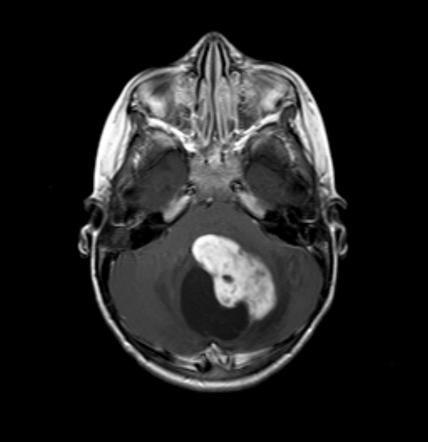

Juvenile Pilocytic Astrocytoma

It is another type of brain tumor that occurs more commonly in children than adults. This tumor is not the most common, but it is remarkable because it has a survival rate of 96% after 5 years, which is one of the highest in any brain tumor. This one is not a solid mass but instead a fluid-filled tumor, often called a cyst. It is a benign tumor with a very slow growth, and it does not spread to other areas of the brain.

It usually appears in the cerebellum or the brainstem, and give out symptoms such as headaches, seizures, nausea, and vomiting. Depending on the location they can cause vision problems, hormonal changes, balance and coordination problems, and many other symptoms.